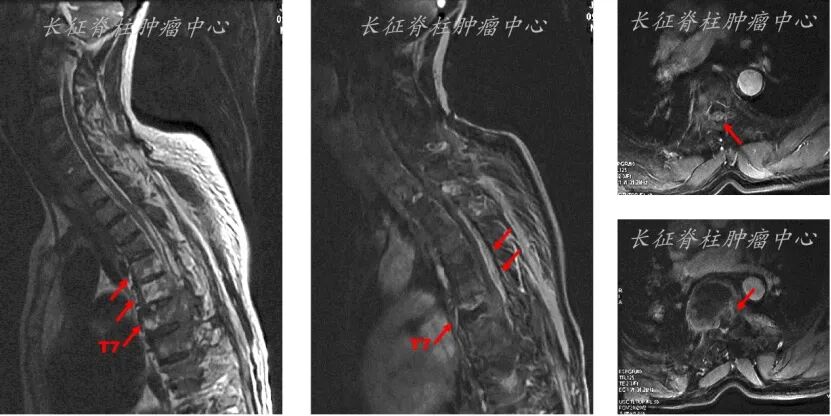

2021.01.05查全脊柱MRI示:胸6-7转移瘤伴硬膜囊明显受压;

MRI:胸5-9椎体信号异常,T7椎体压缩骨折,T4-8椎管内占位。

图2. MRI检查结果